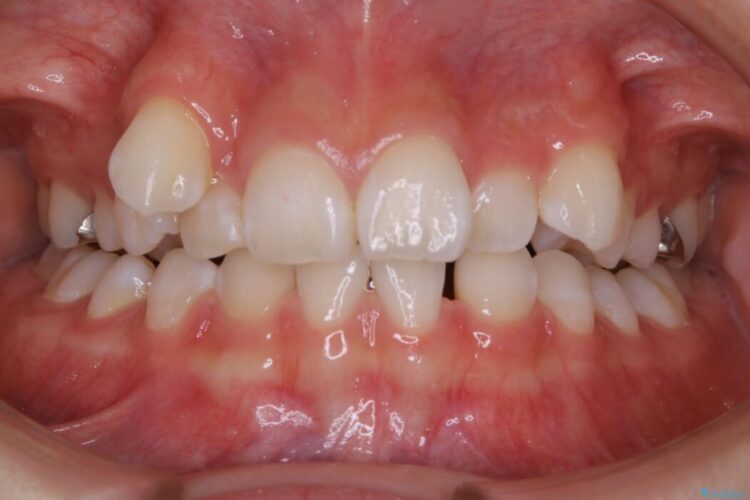

飛び出た八重歯による歯列のガタガタを主訴に来院されました。

診査したところ叢生だけでなく生まれつき永久歯の欠損、いわゆる先天欠如により歯の本数が少ないため噛み合わせなどにも影響が出ている状態でした。